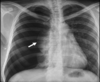

Neumonía bacteriana (radioopacidad)

Neumonía lobar (usualmente por S. pneumoniae)

Neumonía segmentaria (bronconeumonía) por S. aureus Aspecto algodonoso